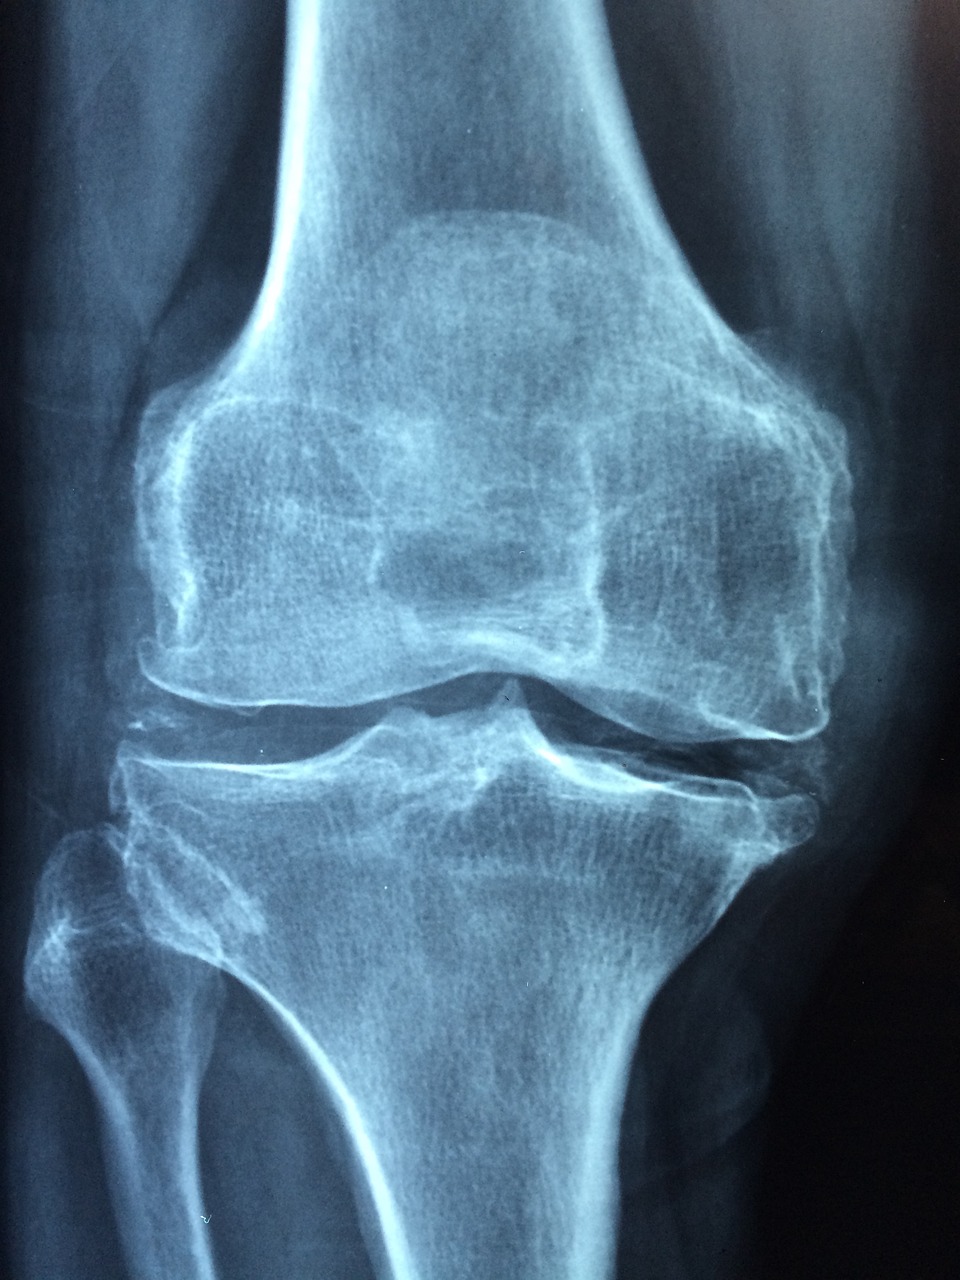

위에서 이야기한 것처럼 파골세포를 억제하는 기능이 있습니다. 인체는 노화가 지속될수록 골아세포보다는 파골세포의 활동이 더 활발하게 됩니다. 갱년기를 넘어가는 나이부터 생기는 골다공증도 이것이 원인입니다. MBP는 이러한 파골세포의 활동을 억제하여 골다공증을 예방하는데 도움이 됩니다.

파골세포의 활동을 억제하는 만큼 골아세포의 활동은 증가시킵니다. 이는 골밀도와 강도를 개선시킵니다. 그렇기에 골다공증을 예방하고 뼈를 더 튼튼하게 만드는데 도움이 됩니다.